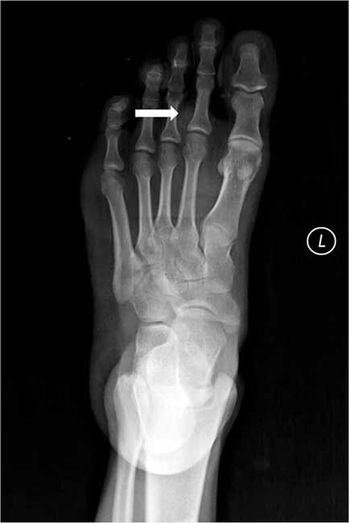

Case History: 38-year-old male with complaints of foot swelling and dull, vague pain.